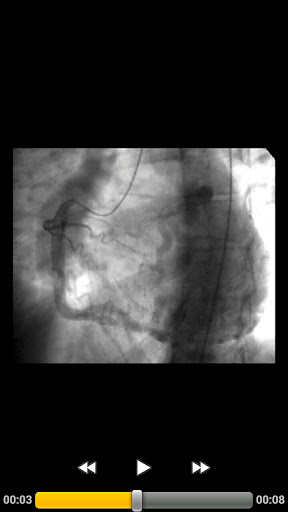

CARDIO3® Atlas of Interventional Cardiology is a CARDIO3®INVASIVE project – reference/learning tool for cardiologists, cardiac surgeons, internists, other physicians evaluating interventional images in cardiology.

- 300 annotated videos (September 2011) and growing